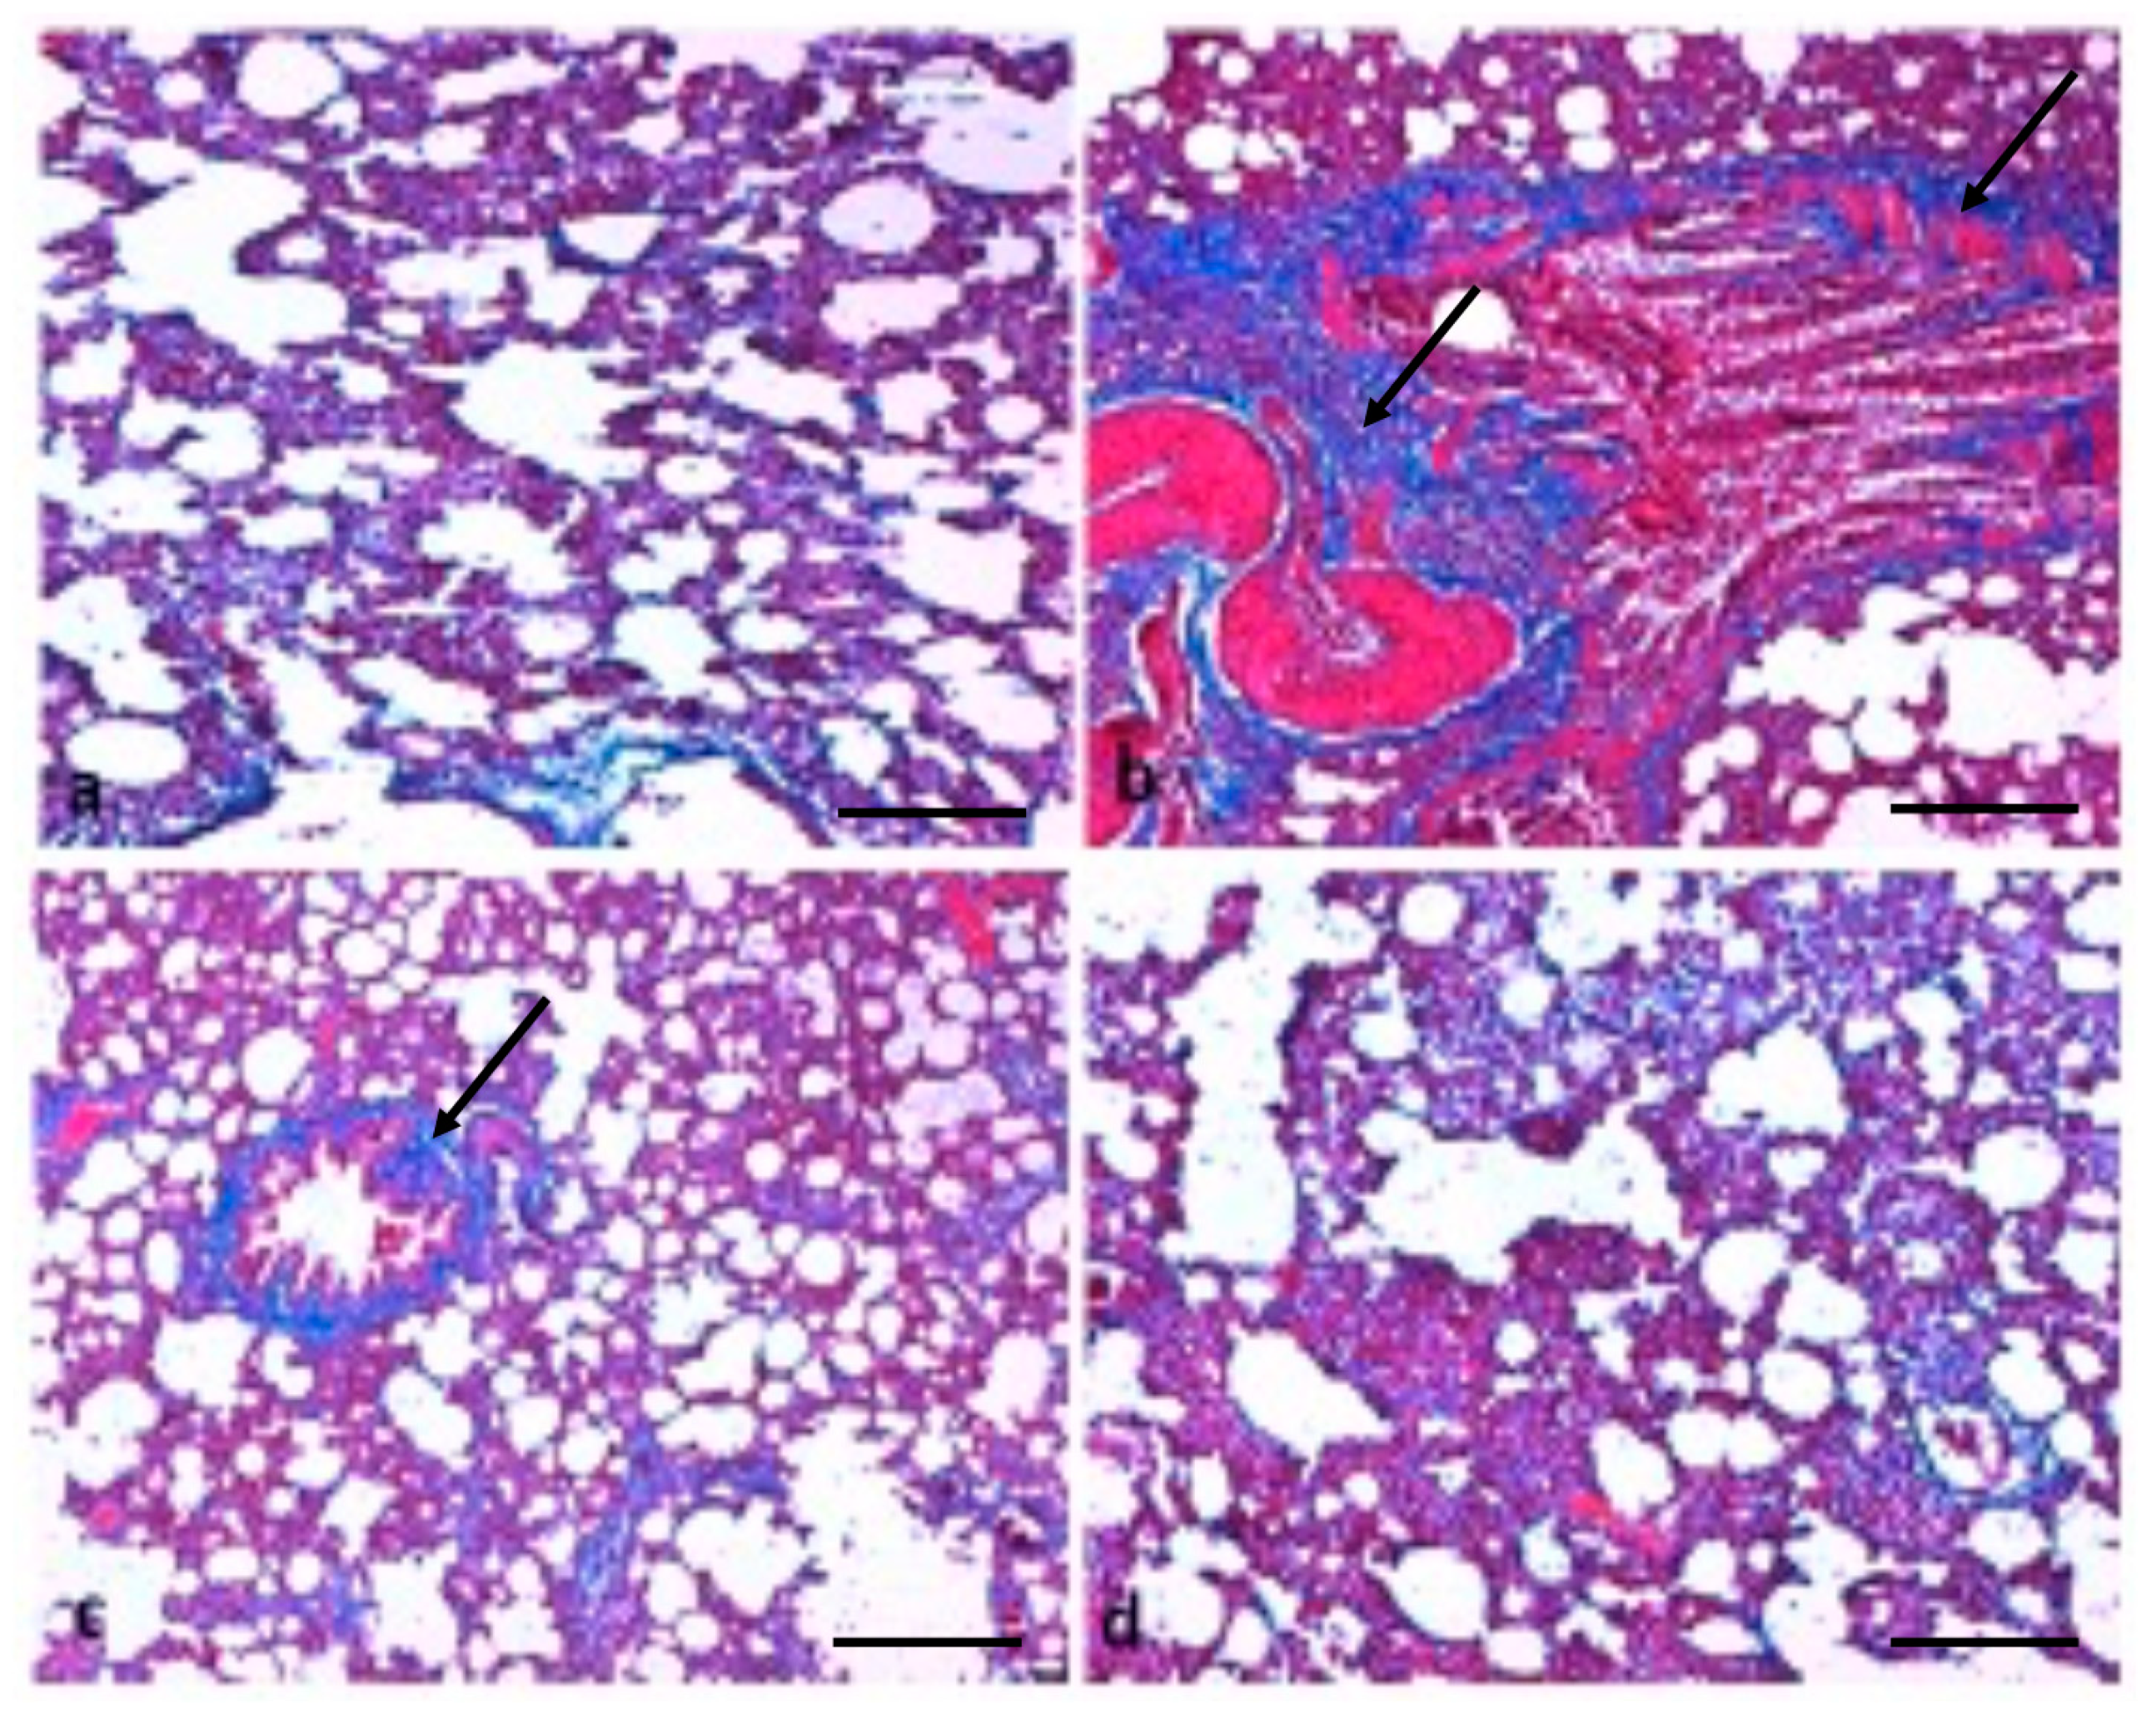

The consequence of TQ on lung fibrosis was also measured by staining collagen fibres using Masson’s trichrome stain. The collagen staining showed that B(a)P administration induced severe collagen deposition (Figure 7); furthermore, such lesions were decreased by treatment with TQ. TQ administration showed suppression of B(a)P-induced fibrosis, as confirmed by Masson’s trichrome staining.

Another study based on B(a)P treatment resulted in the thickening of the lung epithelium compared to the control animals. Moreover, a mass infiltration of inflammatory cells was found in B(a)P-administered animals. The treatment with diosmin led to protection against B(a)P-induced lung tissue pathological changes [37]. In the present study, it was observed that B(a)P treatment induced severe collagen deposition; furthermore, such lesions were decreased by treatment with TQ. Additionally, Sirius red staining demonstrated that fibrosis levels were more in B(a)P-treated lung tissue rats, whereas fibrosis formation was found to be ameliorated in the TQ administration group rats. Another study demonstrated that control group rats revealed normal architecture, while lung cancer-induced animals demonstrated hyperproliferative cells with enhanced deposition of collagen. Pretreatment with capsaicin noticeably minimized the collagen accumulation, thereby preserving the near-normal architecture [38]. Some previous findings have shown that TQ-treated animals show a reduction in the thickening of interalveolar septa, interstitial inflammatory edema, inflammatory exudates in the lumens of airways, and alveoli of bronchial-associated lymphoid tissue [39].

Figure 7. Effect of TQ on lung fibrosis. (a) Normal fibre architecture of lung in control animals; (b) B(a)P administration induces severe collagen deposition; the arrow indicates high deposition of collagen fibers (c) TQ shows suppression of B(a)P-induced fibrosis; the arrow indicates less deposition of collagen fibers. (d) normal collagen in the group treated with TQ only. (Scale bar = 100 μm).